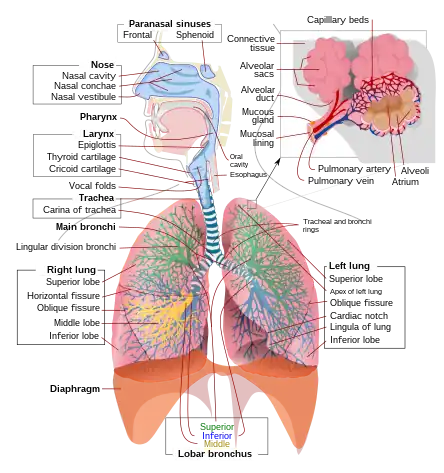

The respiratory tract is divided into the upper airways and lower airways. The upper airways or upper respiratory tract includes the nose and nasal passages, paranasal sinuses, the pharynx, and the portion of the larynx above the vocal folds (cords). The lower airways or lower respiratory tract includes the portion of the larynx below the vocal folds, trachea, bronchi and bronchioles. The lungs can be included in the lower respiratory tract or as separate entity and include the respiratory bronchioles, alveolar ducts, alveolar sacs, and alveoli.[3]

The upper respiratory tract can refer to the parts of the respiratory system lying above the sternal angle (outside of the thorax),[4] above the vocal folds, or above the cricoid cartilage.[5][6] The larynx is sometimes included in both the upper and lower airways.[7] The larynx is also called the voice box and has the associated cartilage that produces sound. The tract consists of the nasal cavity and paranasal sinuses, the pharynx (nasopharynx, oropharynx and laryngopharynx) and sometimes includes the larynx.

The lower respiratory tract or lower airway is derived from the developing foregut and consists of the trachea, bronchi (primary, secondary and tertiary), bronchioles (including terminal and respiratory), and lungs (including alveoli).[8] It also sometimes includes the larynx.

The lower respiratory tract is also called the respiratory tree or tracheobronchial tree, to describe the branching structure of airways supplying air to the lungs, and includes the trachea, bronchi and bronchioles.[9]

- trachea

- main bronchus (diameter approximately 1 – 1.4 cm in adults)[10]

- lobar bronchus (diameter approximately 1 cm)

- segmental bronchus (diameter 4.5 to 13 mm)[10]

- subsegmental bronchus (diameter 1 to 6 mm)[10]

At each division point or generation, one airway branches into two smaller airways. The human respiratory tree may consist on average of 23 generations, while the respiratory tree of the mouse has up to 13 generations. Proximal divisions (those closest to the top of the tree, such as the bronchi) mainly function to transmit air to the lower airways. Later divisions including the respiratory bronchiole, alveolar ducts, and alveoli, are specialized for gas exchange.

The trachea is the largest tube in the respiratory tract and consists of tracheal rings of hyaline cartilage. It branches off into two bronchial tubes, a left and a right main bronchus. The bronchi branch off into smaller sections inside the lungs, called bronchioles. These bronchioles give rise to the air sacs in the lungs called the alveoli.[11]

The lungs are the largest organs in the lower respiratory tract. The lungs are suspended within the pleural cavity of the thorax. The pleurae are two thin membranes, one cell layer thick, which surround the lungs. The inner (visceral pleura) covers the lungs and the outer (parietal pleura) lines the inner surface of the chest wall. This membrane secretes a small amount of fluid, allowing the lungs to move freely within the pleural cavity while expanding and contracting during breathing. The lungs are divided into different lobes. The right lung is larger in size than the left, because of the heart's being situated to the left of the midline. The right lung has three lobes – upper, middle, and lower (or superior, middle, and inferior), and the left lung has two – upper and lower (or superior and inferior), plus a small tongue-shaped portion of the upper lobe known as the lingula. Each lobe is further divided up into segments called bronchopulmonary segments. Each lung has a costal surface, which is adjacent to the ribcage; a diaphragmatic surface, which faces downward toward the diaphragm; and a mediastinal surface, which faces toward the center of the chest, and lies against the heart, great vessels, and the carina where the two mainstem bronchi branch off from the base of the trachea.

The alveoli are tiny air sacs in the lungs where gas exchange takes place. The mean number of alveoli in a human lung is 480 million.[12] When the diaphragm contracts, a negative pressure is generated in the thorax and air rushes in to fill the cavity. When that happens, these sacs fill with air, making the lung expand. The alveoli are rich with capillaries, called alveolar capillaries. Here the red blood cells absorb oxygen from the air and then carry it back in the form of oxyhaemaglobin, to nourish the cells. The red blood cells also carry carbon dioxide (CO2) away from the cells in the form of carbaminohemoglobin and release it into the alveoli through the alveolar capillaries. When the diaphragm relaxes, a positive pressure is generated in the thorax and air rushes out of the alveoli expelling the carbon dioxide.